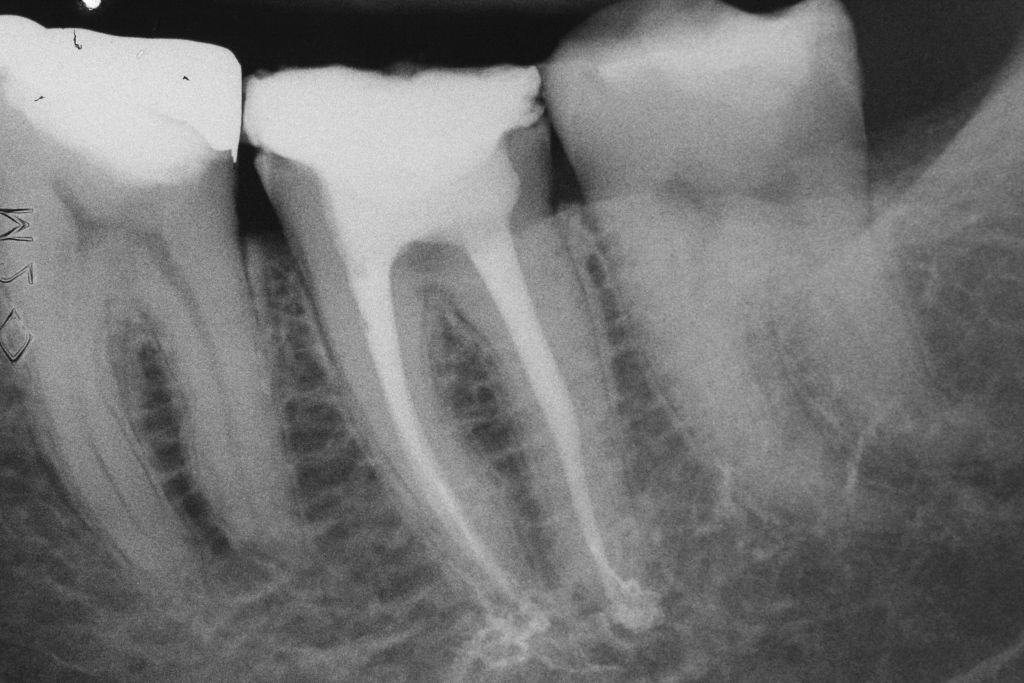

- Figura 1 – Radiografia inicial.

Paciente do gênero feminino, 56 anos de idade e caucasiana compareceu ao consultório se queixando de dor espontânea, pulsátil, que não cessava com o uso de analgésicos e anti-inflamatórios na região de mandíbula esquerda. Apresentou resposta negativa para o teste de palpação apical e percussão vertical e lateral em todos os dentes do referido quadrante. Aos testes térmicos apresentou resposta positiva exacerbada e de longa duração tanto ao frio quanto ao calor apenas no dente 37. Nos outros dentes do quadrante apresentou resposta positiva leve e de curta duração ao frio e negativa ao calor.

Segundo a classificação da Associação Americana de Endodontia, o dente 36 teve um diagnóstico pulpar e periapical de pulpite inflamatória irreversível com periápice normal. O tratamento indicado foi o tratamento endodôntico.